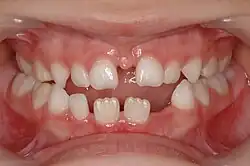

![]() CBCT scan of the maxilla in an 11 year old showing a left alveolar cleft. | |

In cases with a single cleft, 35-60% of lateral incisors are congenitally missing,[4] and cannot be relied on for timing. Instead, the eruption of the incisors and first molars is used as a queue to begin assessments. With bilateral cases, the premaxilla must be repositioned before grafting and special consideration must be given. During this time, the orthodontist must be wary of rotating teeth into the cleft site. Last, the size of the patient, defect, and social issues must all be taken into consideration and is best assessed with a CBCT scan as the patient enters the mixed dentition phase of dental development.[5]